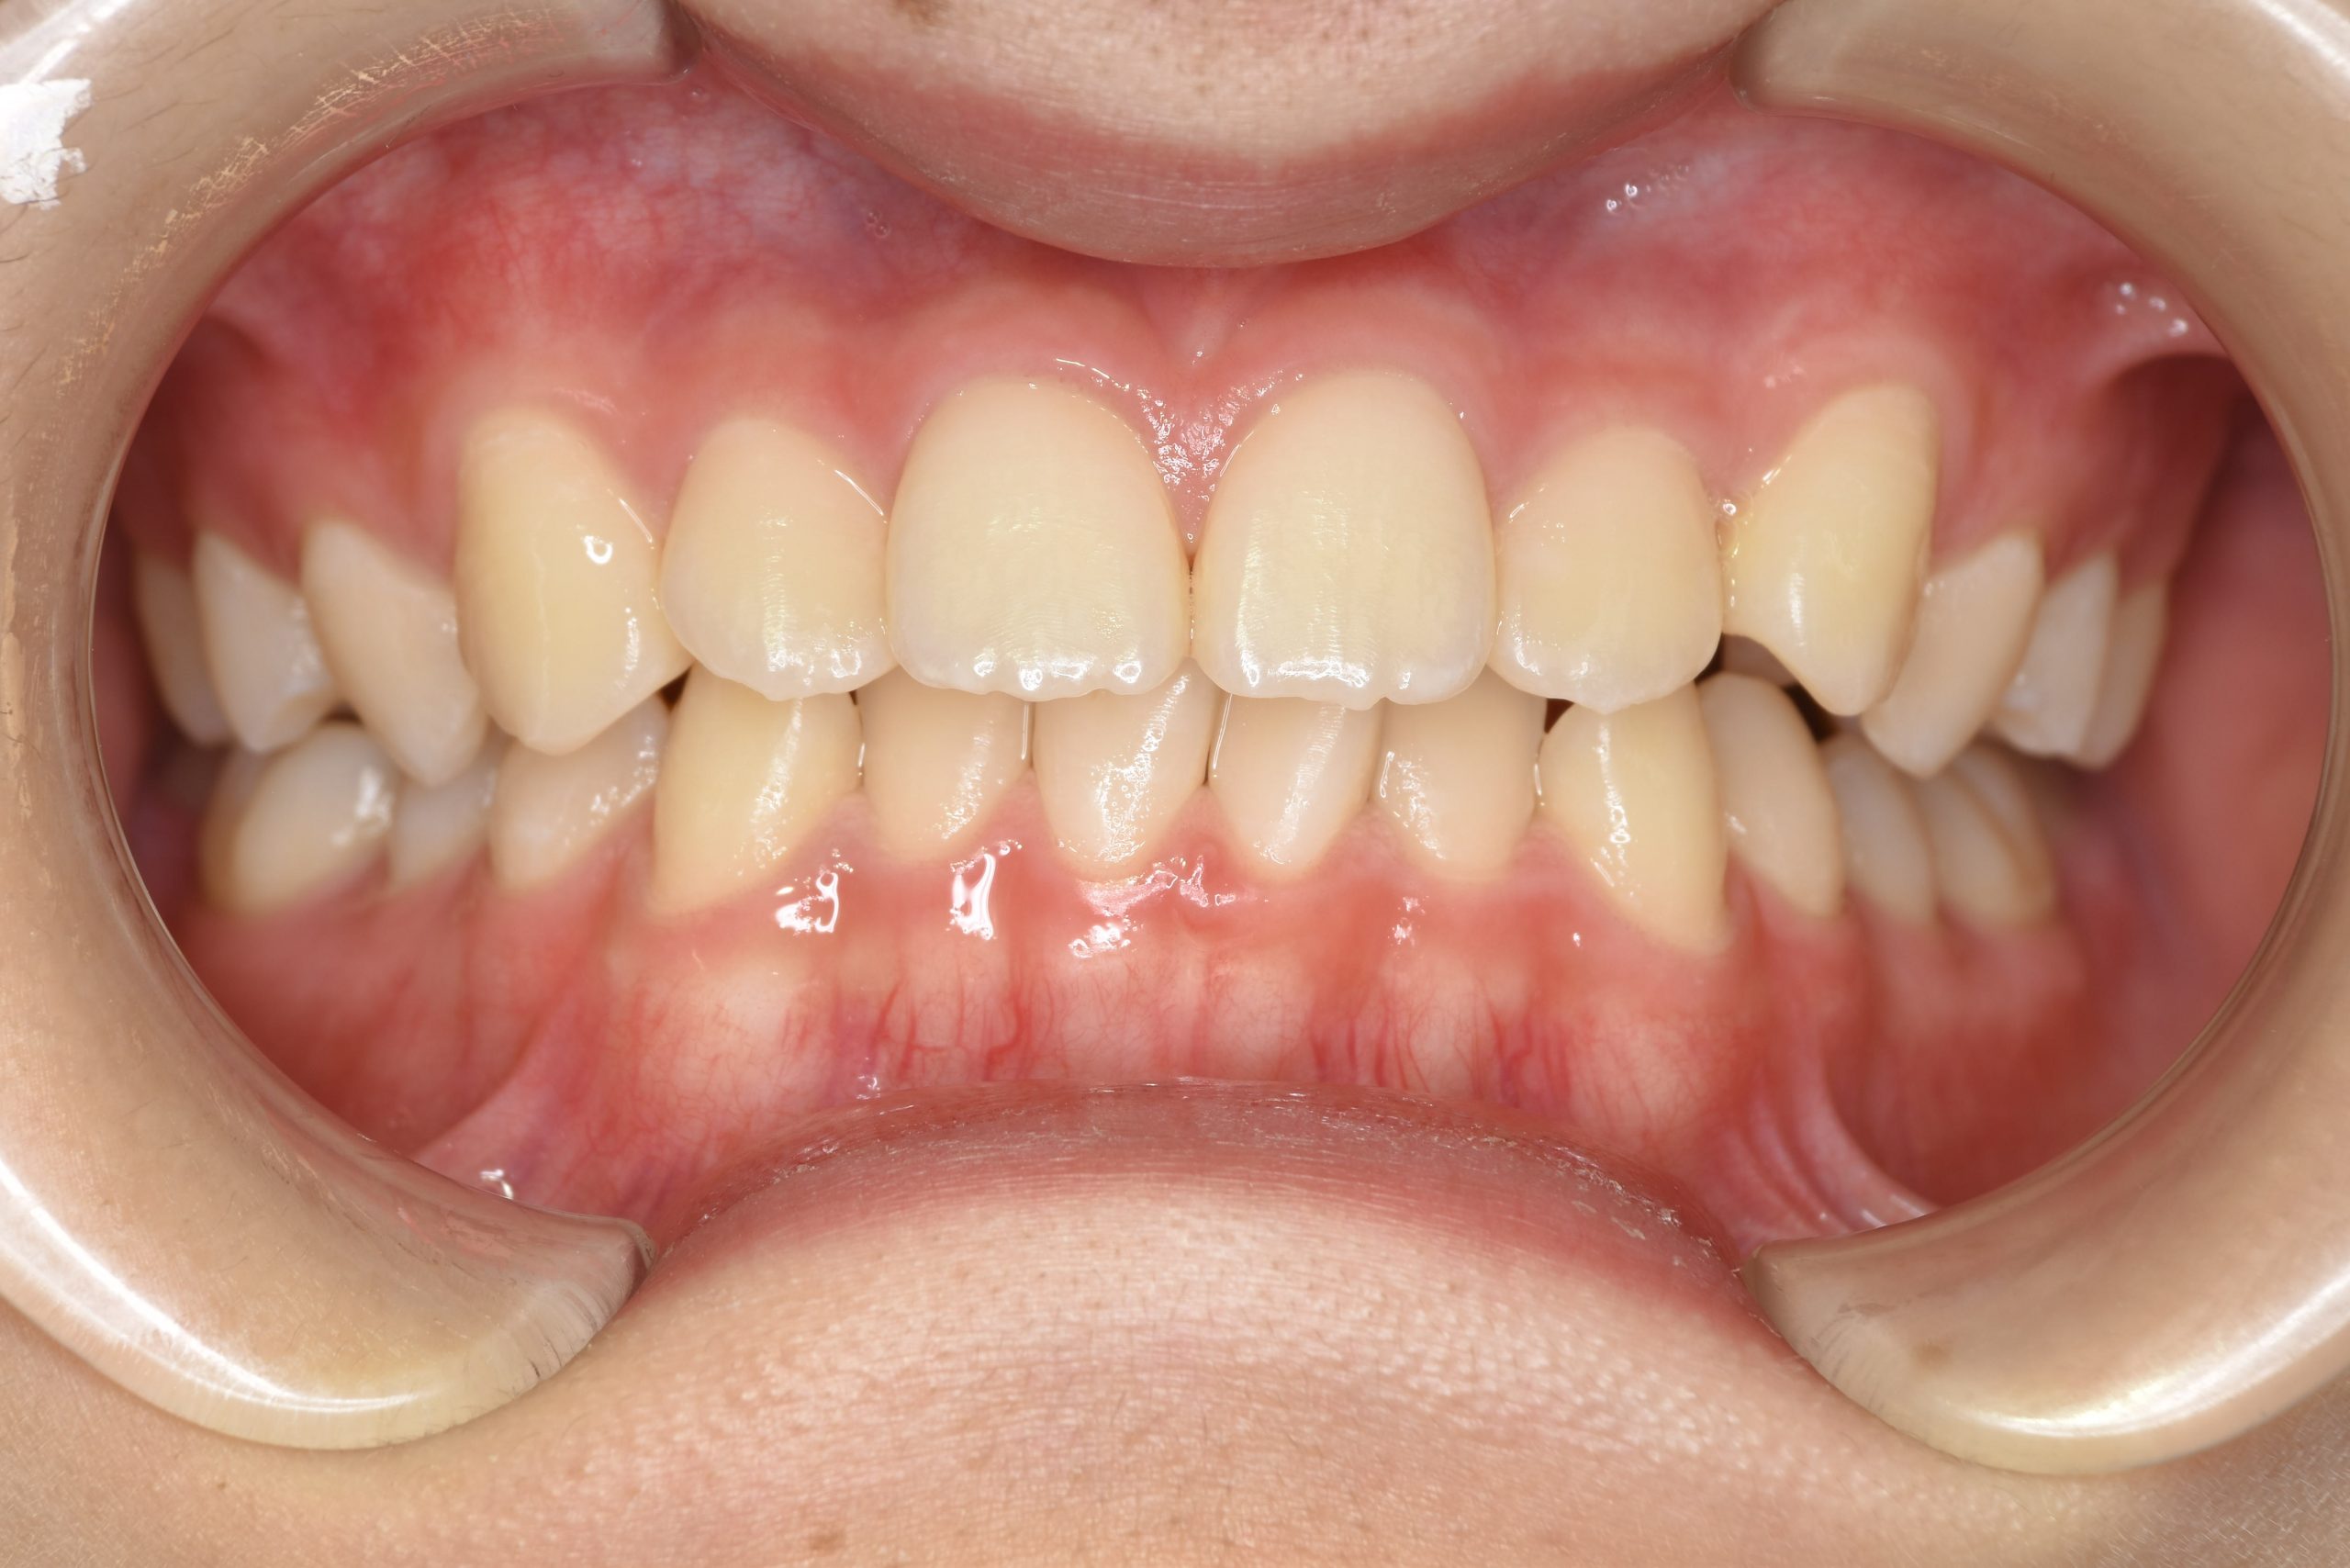

アフター

全顎ワイヤー矯正 症例_185

主訴 歯並び|横から生えている大人の歯

施術内容 小児矯正1期治療

治癒期間 4年間

費用 522,960円(税込)